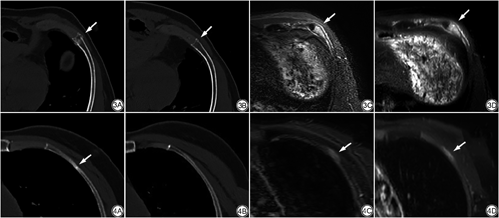

MRI检查共诊断90处骨折,其中3处为假阳性,4处骨折未检出,其诊断准确率为92.55%,敏感度为95.60%。Ⅰ型骨折共85处(3处为假阳性),在STIR及T2-SPAIR序列上表现为“三明治”征,即内层为高信号的骨髓水肿影,中层为低信号的骨皮质,外层为高信号的骨膜下积液;Ⅱ型骨折共5处,表现为高信号的骨髓水肿影,无明显骨膜下积液。

图3及图4分别展示了Ⅰ型与Ⅱ型肋骨骨折在复查CT、首次CT及MRI检查上的表现。

不同于传统的肋骨骨折分型,本研究根据肋骨骨折在复查CT的不同表现提出一种新的分型,Ⅰ型为骨皮质完全或不完全断裂伴外生骨痂和/或骨内骨痂形成,在MRI的压脂序列上表现为高信号的骨髓水肿影伴骨膜下积液形成;Ⅱ型为骨皮质显示完好伴骨内骨痂形成,这是骨小梁发生微骨折的表现,在压脂序列上仅见高信号的骨髓水肿影,无骨膜下积液。骨髓内高信号影是由于骨小梁断裂引起骨髓出血水肿,骨膜下积液可能是骨皮质断裂导致骨膜内的毛细血管破裂出血,血管壁通透性增加,组织液渗出积聚在骨膜下,在低信号的骨皮质周围形成高信号影,积液多者可延肋骨周围蔓延一圈,积液少者可仅聚集在一侧骨皮质周围且为断裂骨皮质一侧。在本研究中,Ⅰ型骨折在首次CT检查上可为阴性(占39.56%),这可能与骨折平面透亮度低[6]和血肿积聚在骨折线周围致使骨折线模糊[14]有关;Ⅱ型骨折由于骨皮质显示完好,仅骨小梁发生了微骨折,故首次CT检查往往不能发现。有学者[15]认为骨小梁微骨折是骨挫伤的表现,但本研究认为骨小梁微骨折属于骨内骨折,应列为Ⅱ型骨折,在临床实际工作中常常漏诊,是一种特殊的隐匿性骨折,需引起重视。本研究所提出的骨折分型的优点是在提高细微肋骨骨折的诊断准确率的同时,还可以利用MRI上肋骨骨折的不同表现判断出骨皮质是否断裂,进一步为临床诊疗工作提供可靠依据。